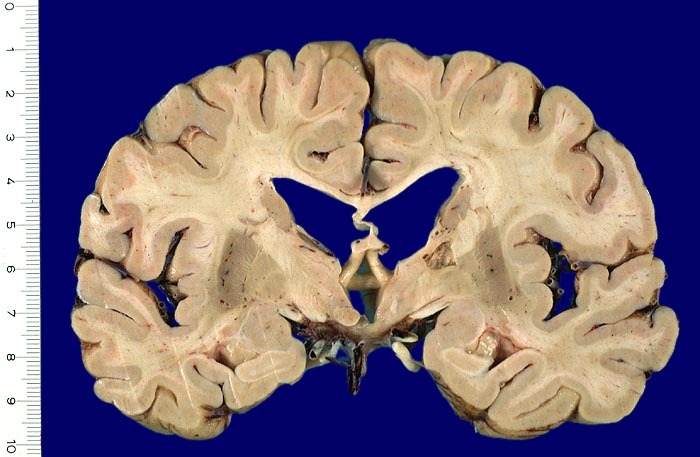

• Organisation und Zystenbildung (ab 1-8 Wochen): Übergänge zum Stadium 2 sind fliessend. Vermehrung von Fettkörnchenzellen rund um proliferierte Kapillaren. Endstadium des anämischen Infarktes bildet ein zystischer Parenchymdefekt, im Gegensatz zu anderen Organen (Herz, Niere) findet kein narbiger Umbau statt. Die in der deutschsprachigen Literatur oft erwähnte "Hirnnarbe" bezieht sich auf die reaktive Gliose im Randbereich des Infarktes. Eine reaktive Gliose ist unspezifisch und findet sich in der Nachbarschaft verschiedener Läsionen (beispielsweise Blutungen, Tumoren, Abszesse etc.). Alte abgebaute Infarkte sollen makroskopisch von alten Kontusionsherden abgegrenzt werden. Diese befinden sich praktisch ausschliesslich in frontobasaler oder temporobasaler Lokalisation (> 1436), wo umschriebene Hirninfarkte nicht vorkommen.

Makroskopie

Befund

Pathologischer Befund

Normalbefund